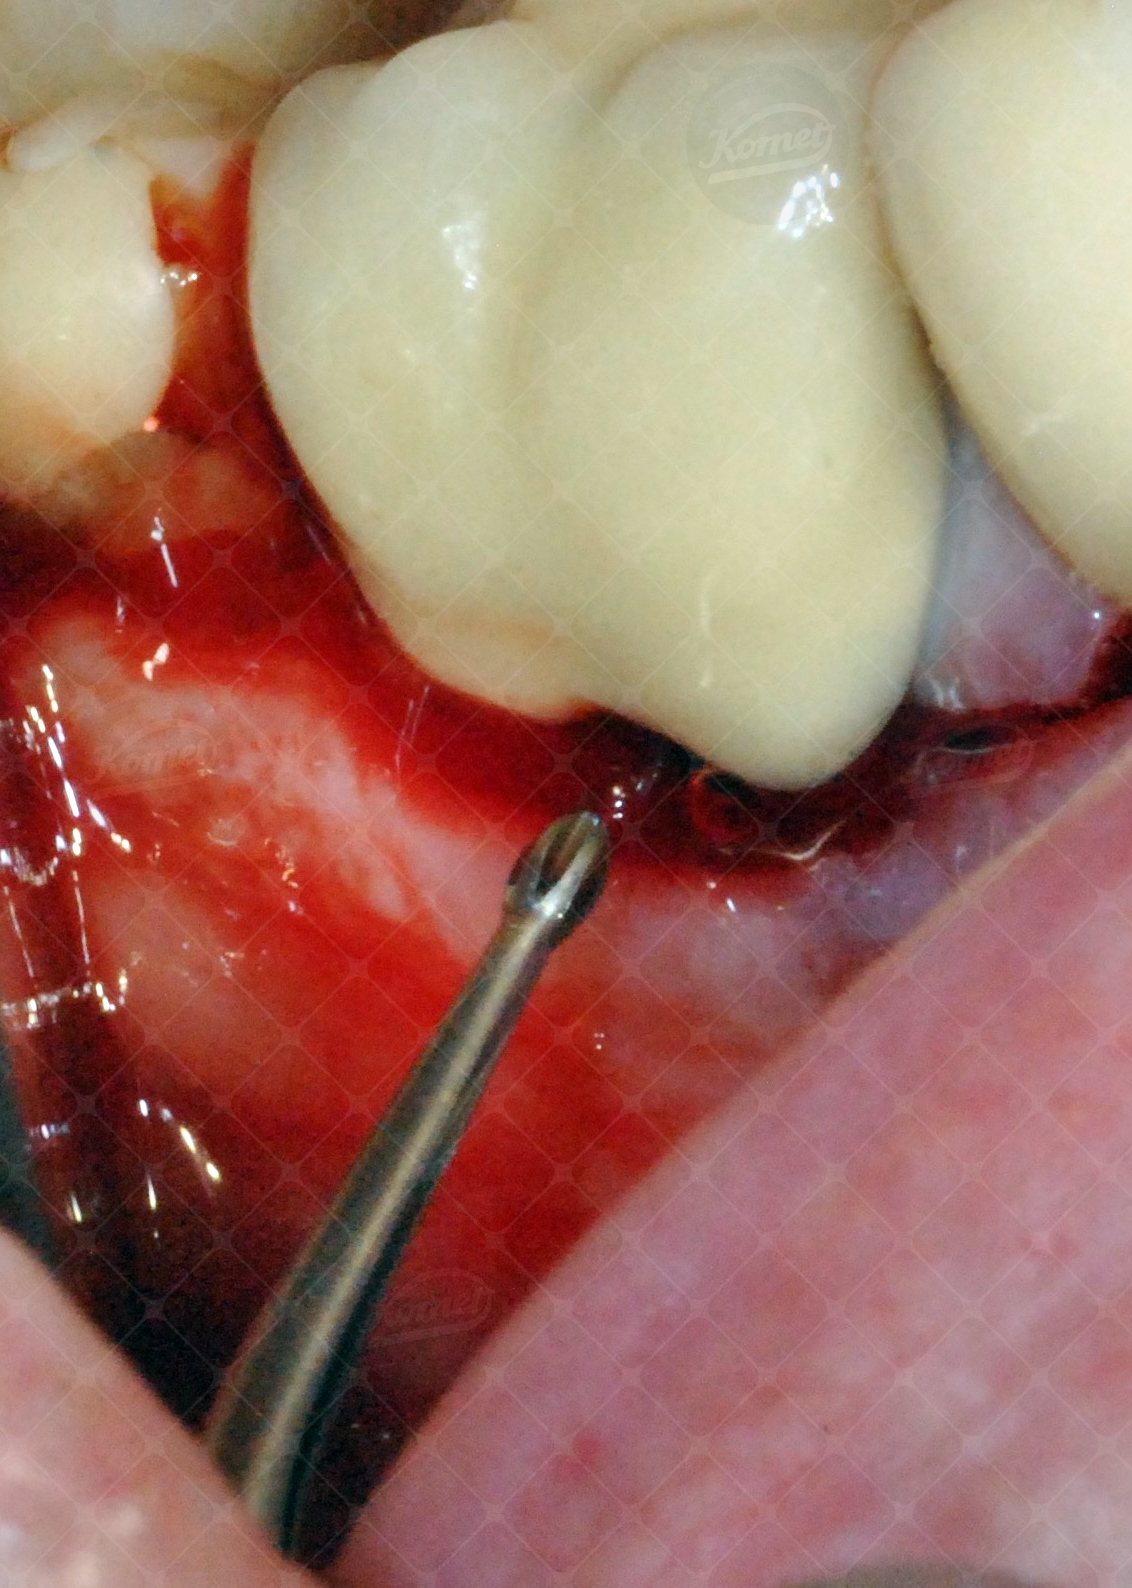

Qui sotto in galleria immagini sono visibili delle foto esplicative del Dr. Salvatore Batia che mostrano l'efficacia delle punte soniche nei trattamenti parodontali.

Dai risultati ottenuti si evince che le punte soniche della serie Komet SF10L/R hanno dimostrato di essere in grado di raschiare la radice del dente con movimenti meno invasivi e con un risultato clinico finale di maggiore recupero parodontale e ridotta sensibilità post-operatoria rispetto ad una levigatura effettuata mediante strumenti manuali. Queste punte soniche, aventi la parte terminale a forma di asola, poggiano sulle radici del dente e lavorano con movimenti delicati e circolari. La parte a contatto con le radici è quella lavorante, mentre la parte esterna è passiva e può essere utilizzata anche a cielo chiuso. Non richiedono movimenti di trazione, infatti grazie al solo movimento sonico è possibile lavorare in modo controllato e delicato sulle radici.